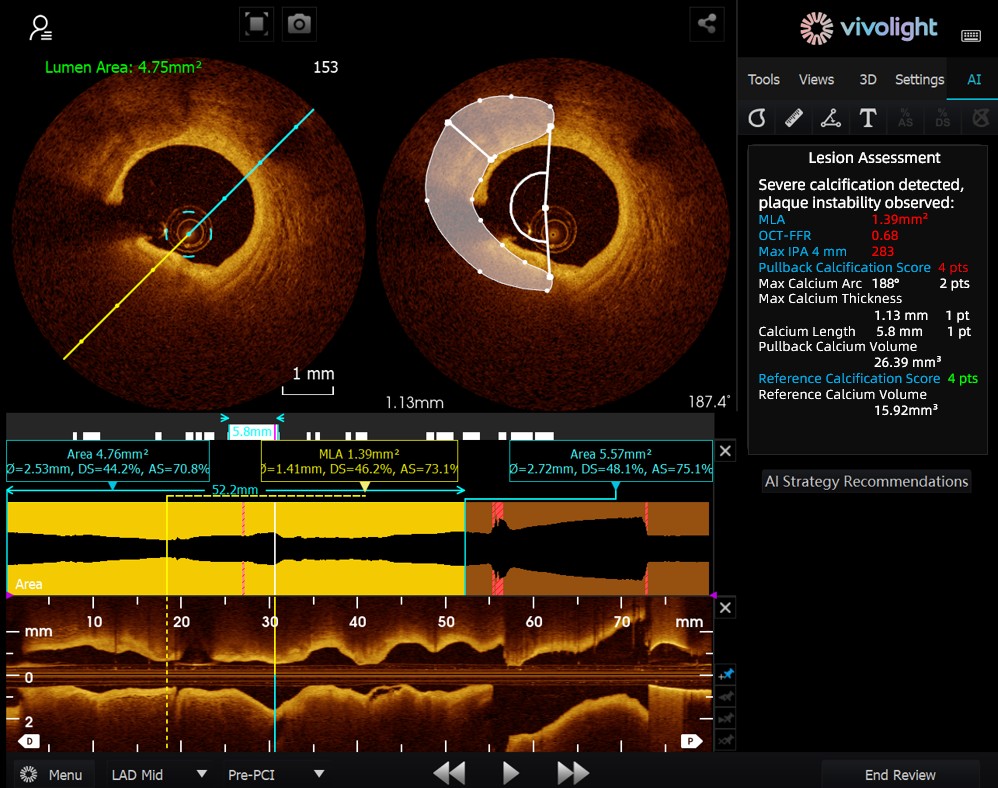

Developed based on Vivolight Medical’s OCT system, the AI-OCT is a next-generation intelligent decision-support system for intravascular imaging. It integrates scattered intravascular imaging diagnostic data—including lumen diameter, culprit lesions, OCT-FFR, and plaque natures—into comprehensive treatment strategies and actionable recommendations. As an independent research software embedded in the OCT platform, it is co-developed with various hospitals to create customized versions tailored to specific clinical needs.

During the cutting-edge forum, experts emphasized that AI-OCT System represents a transformative shift from "viewing images" to "delivering treatment plans"—addressing the challenges of information overload and complex decision-making in cardiac interventional procedures, which traditionally rely heavily on physician experience. Key advantages of the system include:

The AI-OCT System adopts a "small model + big data + large model" architecture: small models enable precise image interpretation, while large models drive comprehensive clinical reasoning. Leveraging high-quality cardiovascular databases and Retrieval-Augmented Generation (RAG) technology, it delivers end-to-end support from lesion assessment to treatment strategy development.